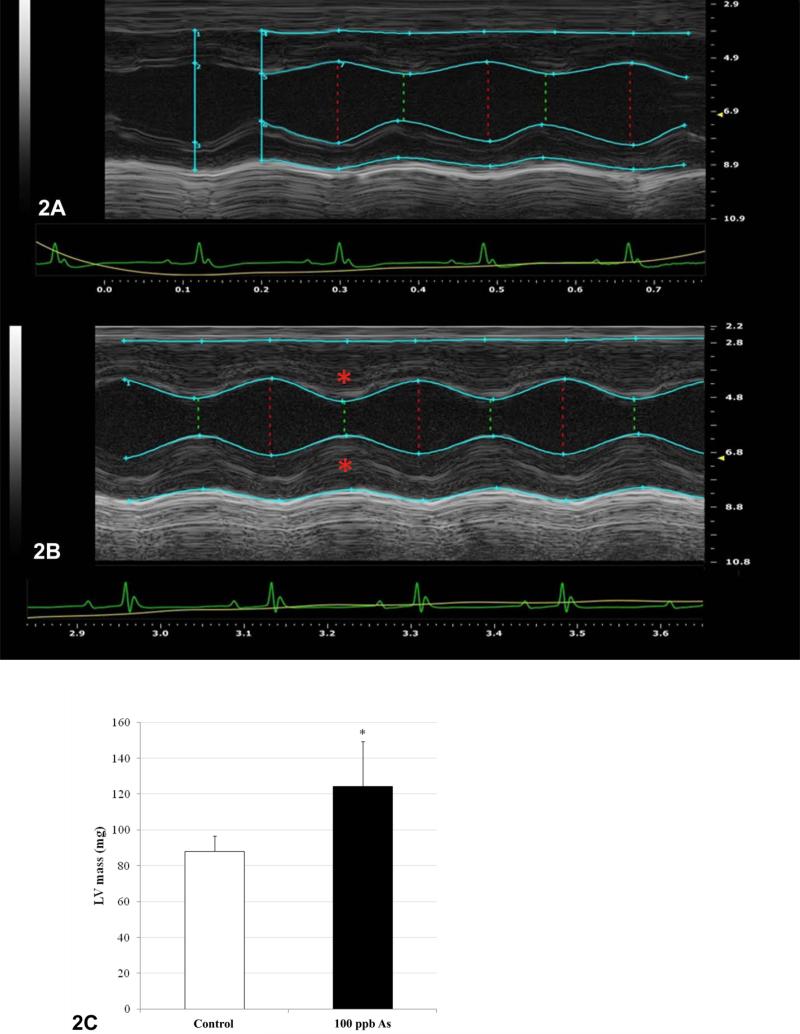

Mice were subjected to echocardiographic analysis after the 22 weeks of arsenic exposure. Representative M-mode images for both controls and arsenic treated mice are shown illustrating tracings of posterior and anterior ventricular walls (FIGURE 2). We calculated the aggregate increase in LV mass in control (FIGURE 2A) and arsenic exposed mice (FIGURE 2B), and found a significant increase of 43% in LV mass in arsenic exposed mice (p <0.05) (FIGURE 2C). Importantly, this increase in LV mass did not correlate with any significant changes in body weight. These observations strongly suggest that arsenic promotes hypertension and subsequent hypertrophic cardiac remodeling. In order to further characterize cardiac changes, IVS lengths were measured in histological sections of hearts from control (FIGURE 3A, C) and arsenic treated mice (FIGURE 3B, D). The average IVS length for control mice was 0.94mm whereas the average IVS length for arsenic treated mice was 1.12 mm. This 19% increase in IVS length was found to be significant (p <0.05) (FIGURE 3E). Histological assessment of interventricular septum supports the echocardiography results showing thickening of the ventricular wall of hearts in arsenic treated mice, which is a hallmark of cardiac hypertrophy.

Figure 2. Echocardiographic analysis shows increased LV mass in arsenic treated mice.

Figure 2A, B. M-mode short axis view of control (panel 2A) and arsenic treated (panel 2B) left ventricle cineloop image. Teal tracings represent LV wall through systole (green dotted line) and diastole (red dotted line). Ventricular wall in treated animals (red asterisks) is substantially thicker than that of control animals.

Figure 2C. Average LV mass from control (white) and arsenic treated (black) mice were calculated as described in the methods section. A significant increase (43% above control) was observed in arsenic treated mice (p ≤ .05).